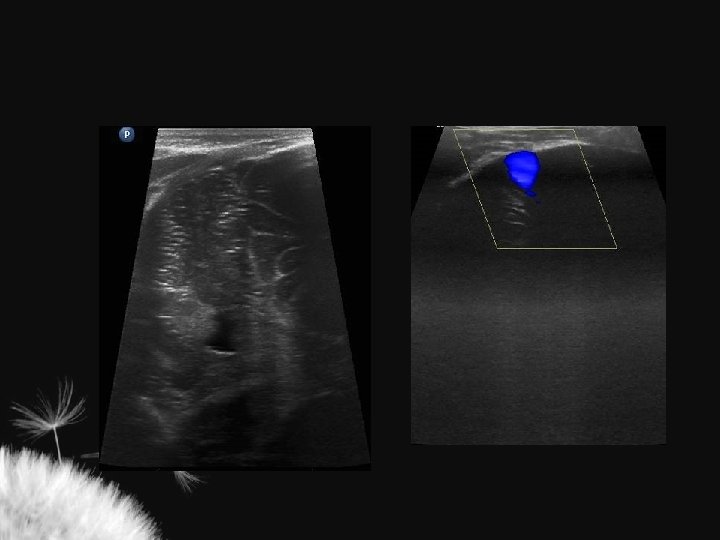

VENTRICULOMEGALIA